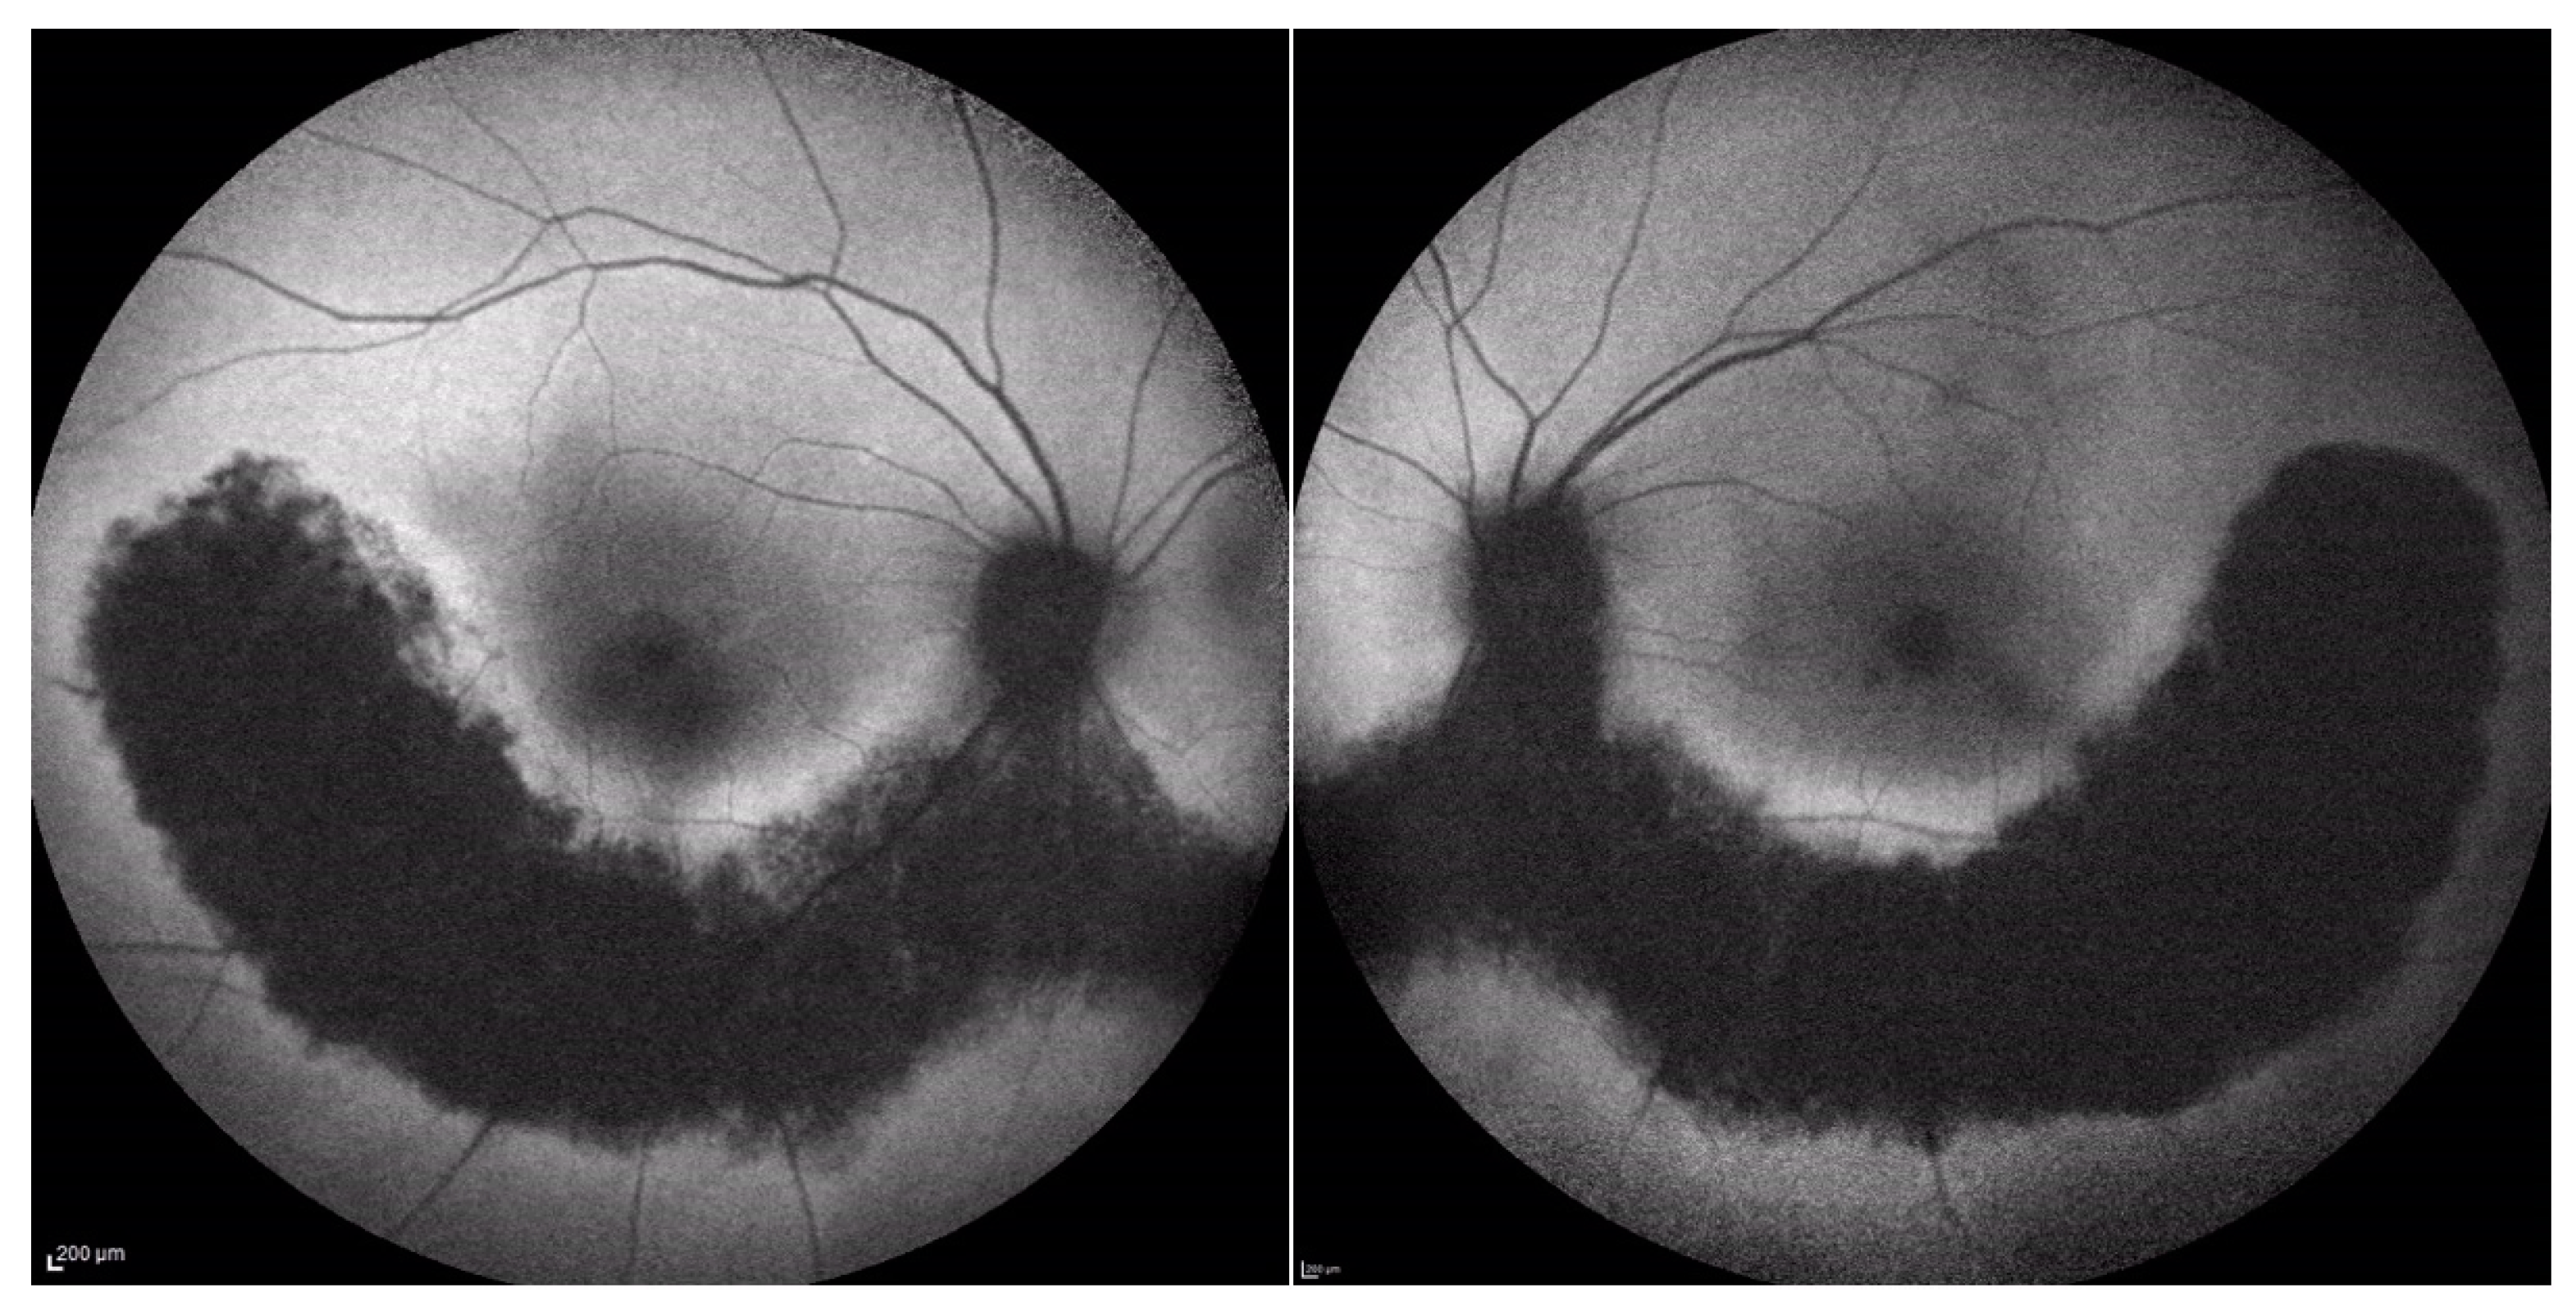

There were no cases of other affected members in the pedigree, except for a deceased brother reported to have visual difficulties. However, no clinical data were available to raise the suspicion of any retinal dystrophy or eye disease. Efforts were made to obtain any clinical records on our systems or previous notes, which were unsuccessful. However, the patients (P.E.) did not report remembering the brother having problems navigating at night light. Additionally, the patient denied consanguinity between his parents, and the progeny did not show any ocular abnormalities, although none of them underwent molecular genetic testing. On examination, BCVA was 0.0 logMAR in both eyes on the first consultation and remained stable over the 7-year follow-up period. Extraocular motility and color vision with the Ishihara plates were also normal. Fundus examination with a slit lamp showed the presence of typical retinal pigment deposits in the form of bone spicules along the inferior and superior vascular arcades with a pericentral concentric pattern. Additionally, there was involvement of the peri-macular area with foveal sparing. In fact, an OCT examination of the macula showed peri-foveal atrophy of the outer retinal layers with the absence of the IS-OS junction and RPE atrophy. A small foveal area with a diameter of 1240 microns in the right eye and 1250 microns in the left eye was spared. This was in agreement with the excellent visual performance of our patient. Central foveal thickness (CFT) at the last OCT examination was 258 microns in the right eye and 259 microns in the left one (Figure 6). Fundus autofluorescence (BAF and GAF) showed areas of hypo-autofluorescence compatible with the diseased and atrophic retina identified on OCT in a specific ‘double ring’ pattern appearance (Figure 7). The infrared module also showed the same characteristic pattern due to the involvement of the deep retinal structures at the level of the RPE (Figure 8).

Figure 7. Fundus autofluorescence (FAF).